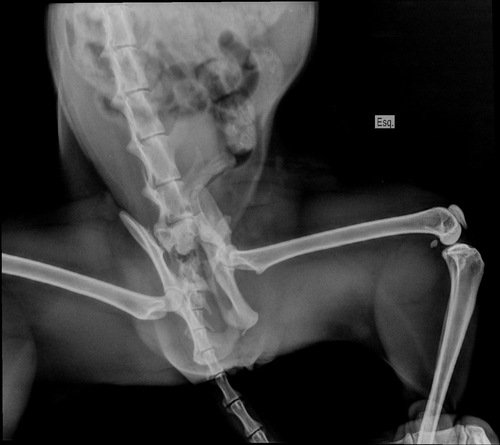

Preciso arrecadar esse valor para realizar a cirurgia da Cora! Ela caiu do 6° andar e precisa da cirurgia com urgência para poder defecar e urinar, pois quebrou o osso da pélvis e teve uma luxação!